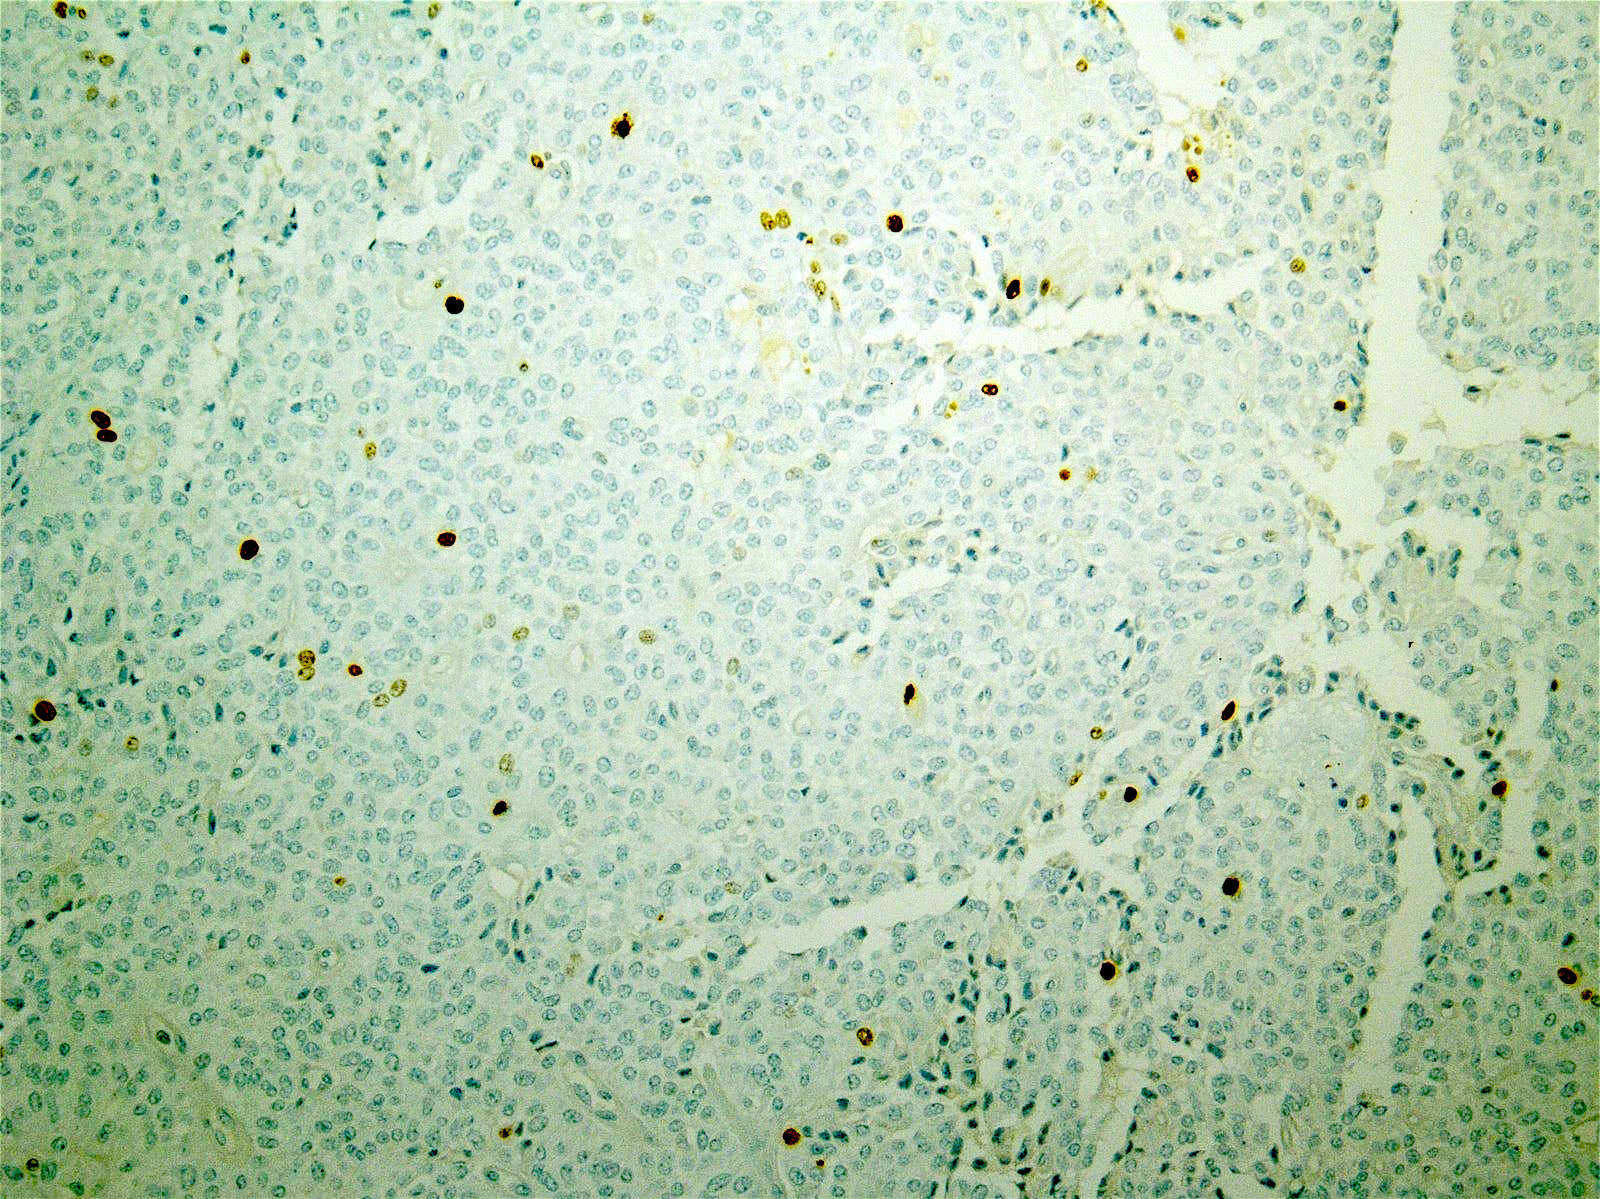

Microscopic (histologic) images

Contributed by Monika Vyas, M.D., Omid Savari, M.D. and Raul S. Gonzalez, M.D.

Positive stains

- Beta catenin (98%): aberrant nuclear expression

- Point mutation in exon 3 of β catenin gene (CTNNB1) is present in > 90%

- Gene mutation results in the accumulation of β catenin in the cytoplasm and formation of a β catenin Tcf / Lef complex, through which the Wnt signaling pathway activates several oncogenic genes, such as MYC and cyclin D1 (Am J Clin Pathol 2017;149:67)